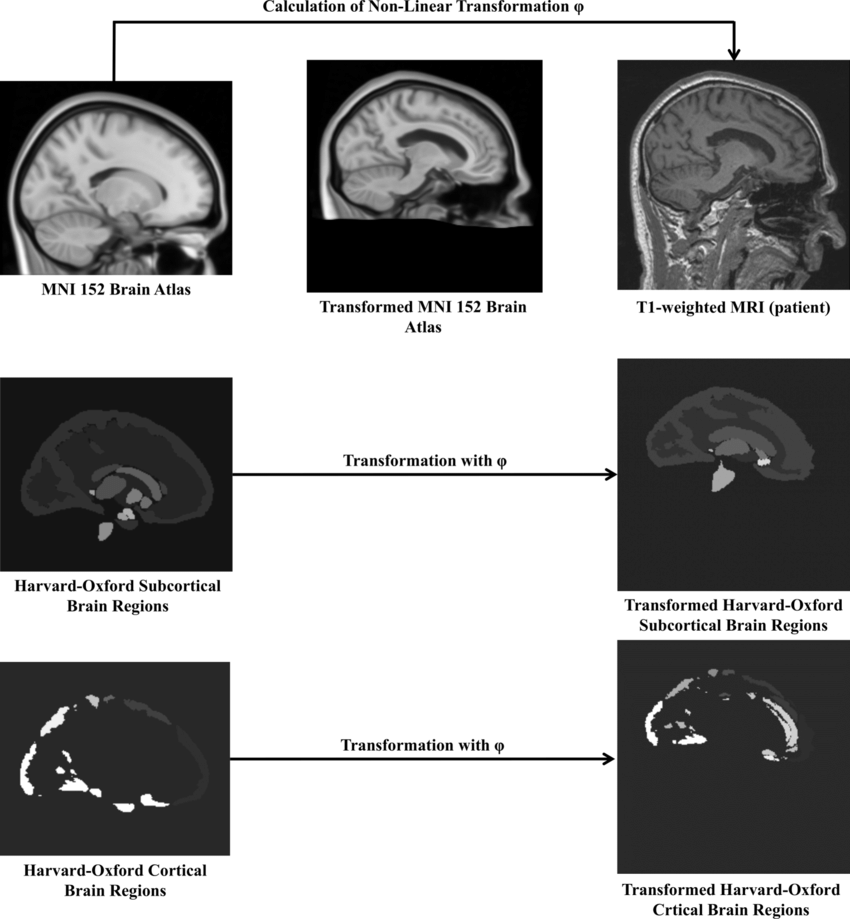

Parkinsonian syndromes encompass a spectrum of neurodegenerative diseases, which can be classified into various subtypes. The differentiation of these subtypes is typically challenging. The aim of this project is to develop image-based classification methods of patients with Parkinson’s disease on diffusion-tensor magnetic resonance imaging (MRI).

Aron S. Talai, Zahinoor Ismail, Jan Sedlacik, Kai Boelmans, Nils D. Forkert: Improved automatic morphology-based classification of Parkinson’s disease and progressive supranuclear palsy - Richardson's syndrome. Clinical Neuroradiology, 29(4), 605-614, 2019.

Aron S. Talai, Jan Sedlacik, Kai Boelmans, Nils D. Forkert: Widespread diffusion changes differentiate Parkinson's disease and progressive supranuclear palsy. NeuroImage: Clinical, 20, 1037-1043, 2018.